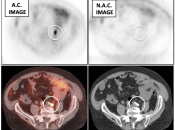

Value of Non-Attenuation Corrected (NAC) Images

Resolving Attenuation Correction Artifacts:

The CT images obtained during an exam are not only used for “anatomic” interpretation. They are also used for “attenuation correction” (AC) of the PET images, generating the much more useful AC PET images used for interpretation.

Unfortunately, attenuation correction of PET images can result in falsely elevated metabolic activity in regions of high CT density (e.g. metallic devices, oral contrast, calcification).

In such cases, these areas must be reviewed on the NAC (non-attenuation correction) images. If these regions are not also hypermetabolic on the NAC images, then their apparent increased FDG-uptake on the AC images is artefactual.

This phenomenon is almost exclusively seen with older PET/CT scanners, as most modern scanners utilize newer algorithms that do not “over-correct” in these areas of increased density.